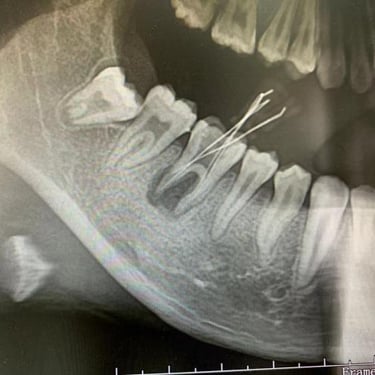

Perforación Radicular

Una perforación radicular es una abertura anormal en la raíz del diente, generalmente debido a un procedimiento dental fallido o una caries profunda.

Los pacientes pueden sentir dolor y notar hinchazón en la encía.

El tratamiento incluye la reparación de la perforación y el tratamiento de conducto. Es crucial reparar la perforación para evitar una infección.